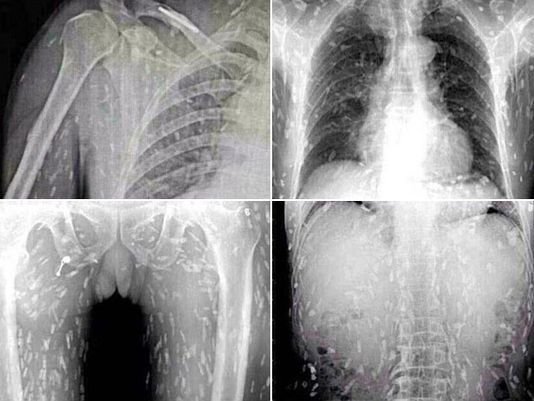

หนุ่มจีนชอบกินปลาดิบสุดช็อก หลังเอกซ์เรย์เจอพยาธิทั่วตัว

เมื่อวันที่ 24 กันยายน 2557 เว็บไซต์เดลี่เมลของอังกฤษ เปิดเผยเรื่องราวสุดน่าสะพรึงของชายจีนรายหนึ่งโปรดปรานเมนูปลาดิบมาก แต่เมื่อไปพบแพทย์ต้องช็อกเมื่อพบว่าร่างกายมีพยาธิอยู่ทั่วทั้งตัว แพทย์ชี้อาจเป็นเพราะทานปลาดิบที่ไม่สะอาดและทานปลาดิบมากเกินไป             รายงาน ระบุว่า ชายจีนจากเมืองกวางโจว มณฑลกวางตุ้ง ซึ่งไม่ได้รับการเปิดเผยชื่อรายนี้ เป็นคนที่ชื่นชอบการทานปลาดิบเอามาก ๆ เขาทานปลาดิบเป็นประจำ กระทั่งวันหนึ่งเขาเกิดอาการปวดท้องและคันตามผิวหนังอย่างไม่ทราบสาเหตุ จึงรีบไปพบแพทย์เพื่อตรวจดูอาการที่โรงพยาบาลกวางโจว หมายเลข 8 ซึ่งเมื่อแพทย์เอกซ์เรย์ดูก็ต้องอึ้ง เมื่อพบว่าภายในร่างกายของเขามีแต่พยาธิตัวตืดเต็มไปหมด             จากเหตุการณ์ดัง ................... อ่านต่อคลิ๊กที่นี่ ไม่แสดงโฆษณา detail